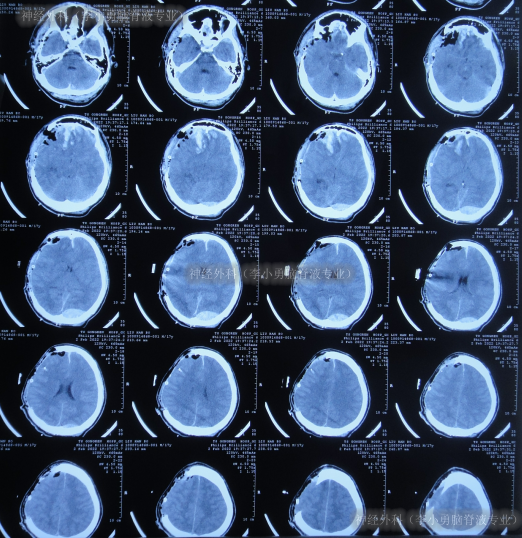

继续治疗1月期间出现数次呕吐,行胃肠镜检查未见异常(片子丢失),给予胃管及肠管置管,期间5次查头颅CT(图-5)均示脑室逐渐出现扩张,并加重。

图-5:5次查头颅CT

去骨瓣减压术后36天即2022年3月9日,复查头颅CT(图-6)示脑室扩张更严重了,脑膨出。

图-6:2022年3月9日头颅CT

去骨瓣减压术后43天即2022年3月16日,查头颅CT示仍严重脑积水(图-7)。

图-7:2022年3月16日头颅CT

因脑积水进一步加重,于2022年3月28日(去骨瓣减压术后55天),进行了脑室腹腔分流术。术后次日查头颅CT示脑室分流术后有出血(图-8)。

图-8:2022年3月29日头颅CT

脑室腹腔分流术后4天即2022年4月1日,查头颅CT示脑室明显缩小(图-9)。

图-9:2022年4月1日头颅CT

脑室腹腔分流术后8天即2022年4月5日,查头颅CT示脑室周仍有水肿(图-10)。

图-10:2022年4月5日头颅CT

脑室腹腔分流术后31天即2022年4月28日,查头颅CT示脑室又变大(图-11)。

图-11:2022年4月28日头颅CT